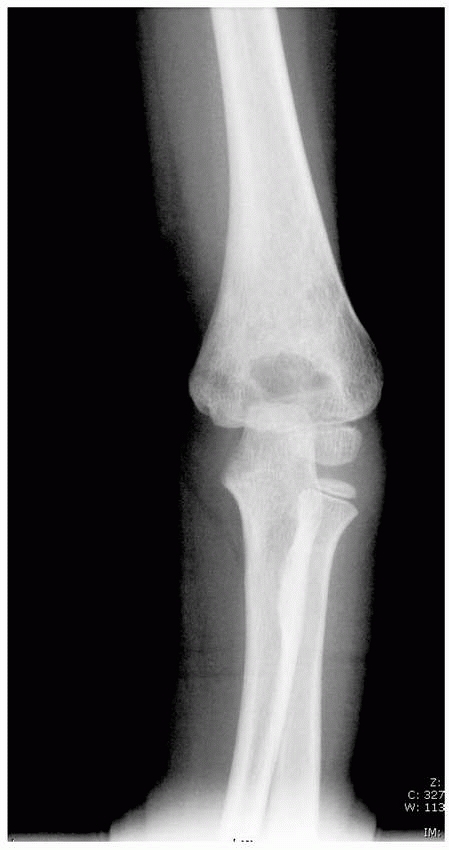

![]() |

FIGURE 14-2

Supracondylar fractures occur through the thinist portion of the distal humerus in the AP plane. The thin bone makes the fracture unstable. |